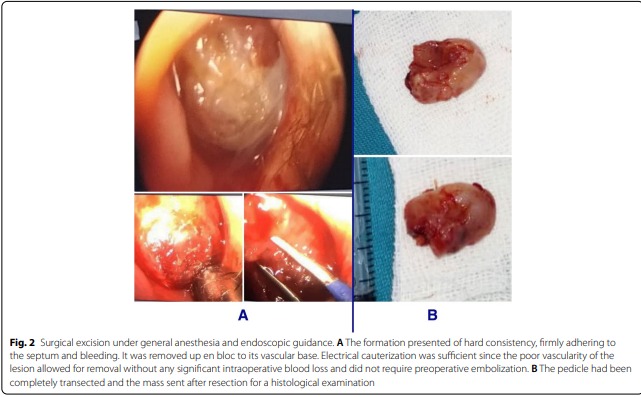

وأضافت الدكتورة يارد لـ “أثر” أنه بعد التقييم السريري والاستقصاءات الشعاعية أُخذ القرار بضرورة التدبير الجراحي تحت التخدير العام وبالجراحة التنظيرية النوعية واستئصل الورم ككتلة واحدة مع التمكن من السيطرة على النزف بالتخثير الكهربائي، وجاءت نتيجة التشريح المرضي مؤكدة تشخيص الورم الوعائي الليفي على حساب الوتيرة الأنفية، وبعد متابعة الطفل على مدى عام كامل بعد الجراحة لم يُلاحظ أي نكس.